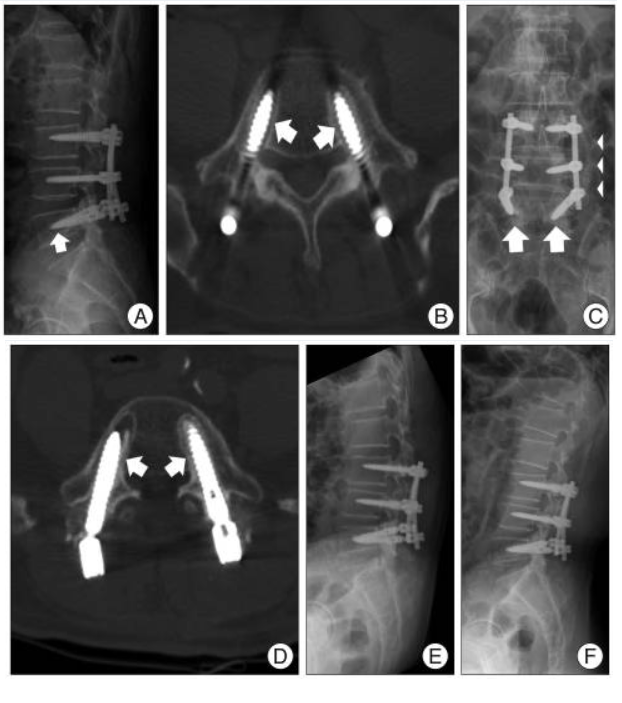

When pedicle screw loosening is confirmed, the choice of corrective procedures depends on the severity of the problem and the patient’s overall health. Options may include revision surgery, physical therapy to address symptoms and improve function, or the use of modified transpedicular screw augmentation. This latter technique involves filling the space around a loosened screw with polymethylmethacrylate (PMMA) bone cement and reinserting a new screw to restore stability. Ultimately, a comprehensive diagnosis using clinical evaluation, imaging, and extraction torque measurement ensures that patients receive the most appropriate and effective care for pedicle screw loosening.

B. Bone Cement Augmentation

For patients with poor bone density, polymethylmethacrylate (PMMA) bone cement can be injected around screws to reinforce fixation.

Kyphoplasty/Vertebroplasty: Cement injection stabilizes the vertebral body and screw interface. Pedicle screw augmented techniques, including the use of fenestrated screws, rely on optimal cement viscosity to ensure proper distribution and minimize complications. The screw cement interface is critical for achieving high pedicle screw fixation strength and preventing loosening.

Effectiveness: A 2018 study reported a 92% success rate in preventing re-loosening with cement-augmented screws (Kim et al., 2018). However, if fixation stability is not achieved, there is a risk of implant failure and hardware failure, necessitating revision surgeries.